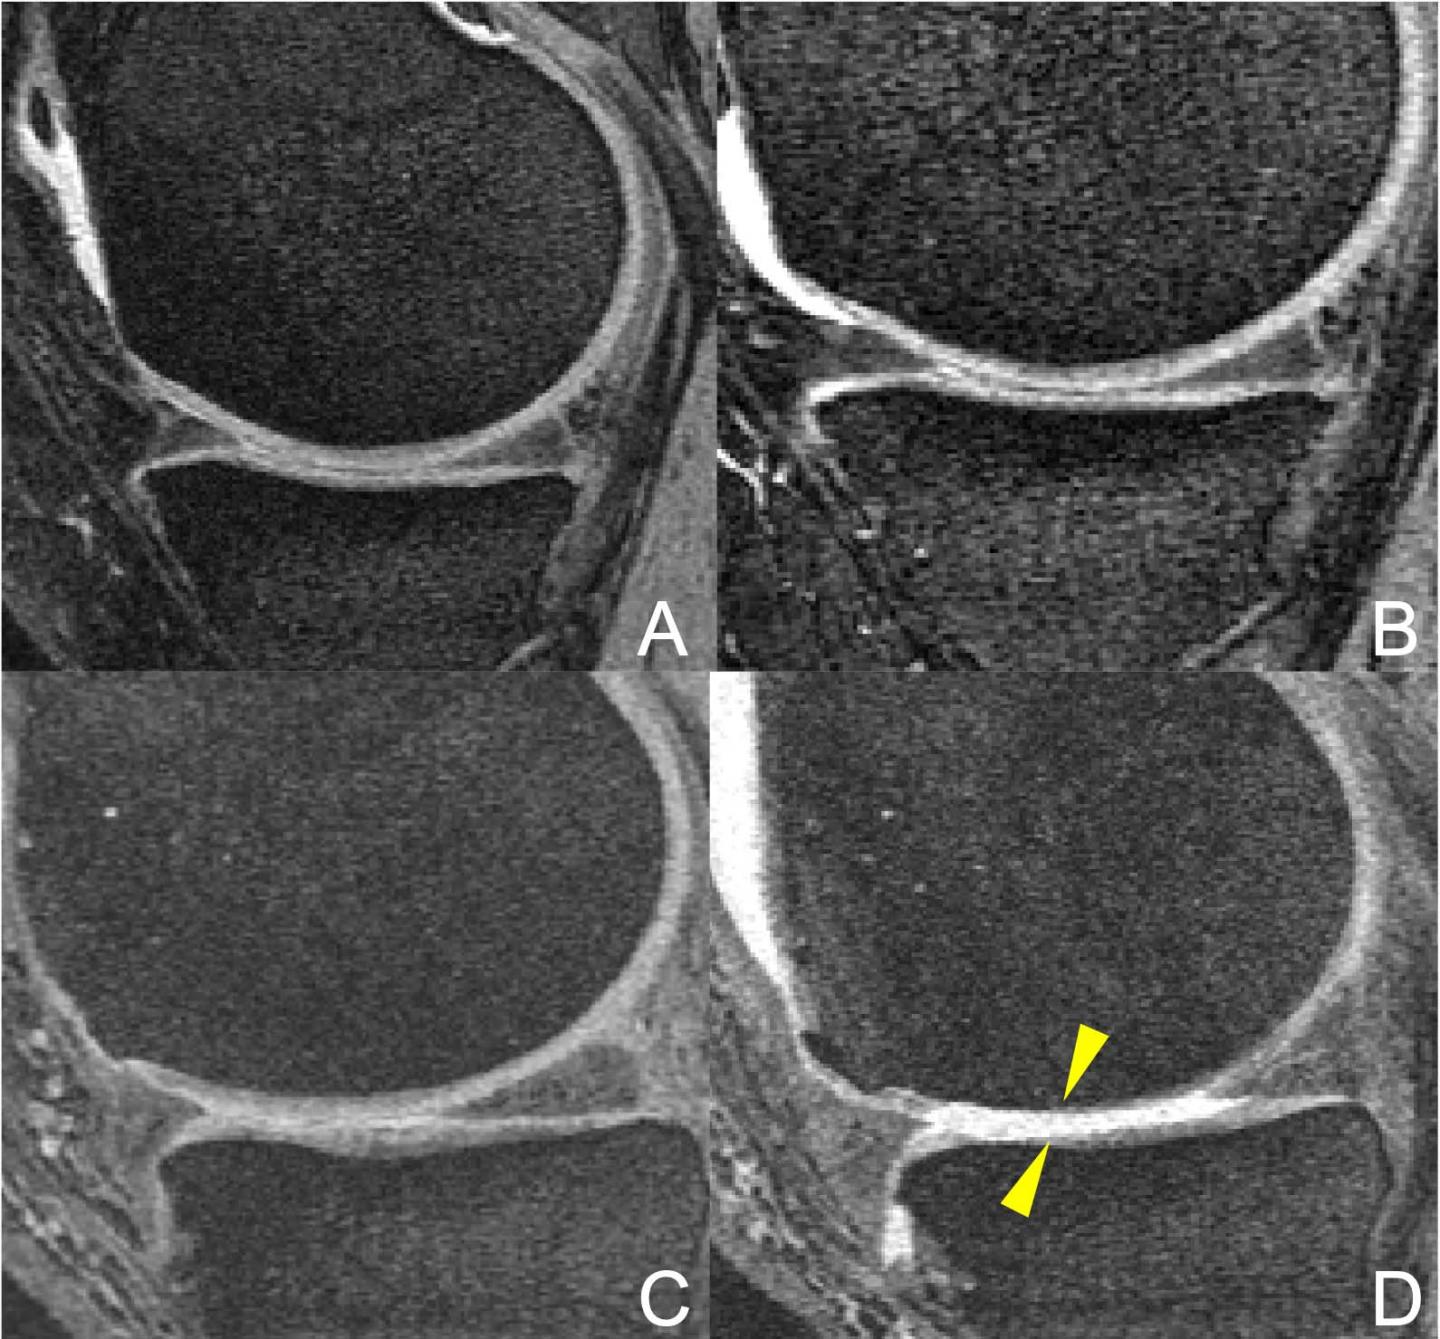

image: MR images of the right knee (A, B, C, D) at baseline (A, C) and after 48 months (B, D). Overweight 47-year-old woman in the elliptical trainer group (A-B) and overweight 64-year-old man in the racket sports group (C-D). The man in the racket sports group developed severe cartilage damage at the femur and tibia bones (arrowheads). In contrast, no cartilage damage was seen in the woman in the elliptical trainer group (A-B).

Patients regularly participating in racket sports saw their overall WORMS score increase significantly, compared to patients regularly using the elliptical trainer over the study period. Surprisingly, the overall WORMS score also increased significantly in the racket sports group compared to the jogging/running group. Racket sports participants saw significantly greater degeneration in the medial tibial cartilage compartment, the compartment on the inside of the knee where arthritis often first appears.

Participants using the elliptical trainer showed the smallest changes in structural degeneration over four years.

The more rapid degeneration of the knee joints in people who participated in racket sports is likely due to the high-speed lateral movements inherent to such sports, Dr. Schirò said. These movements can affect the femoral-tibia compartment, a structure in the knee made up of the femur condyle, the rounded end of the thighbone that helps it slide over the tibia, or shinbone, and the meniscus, the rubbery, C-shaped cartilage between the thighbone and the shinbone.

"A large lateral force imparted at the foot during side-to-side movements may be driving large knee adduction moments, a key feature in medial compartment disease, which imparts high compressive loads on the medial tibia and femoral condyle," she said. "In support of this premise, the racket sports group showed elevated cartilage degeneration in the medial tibia."